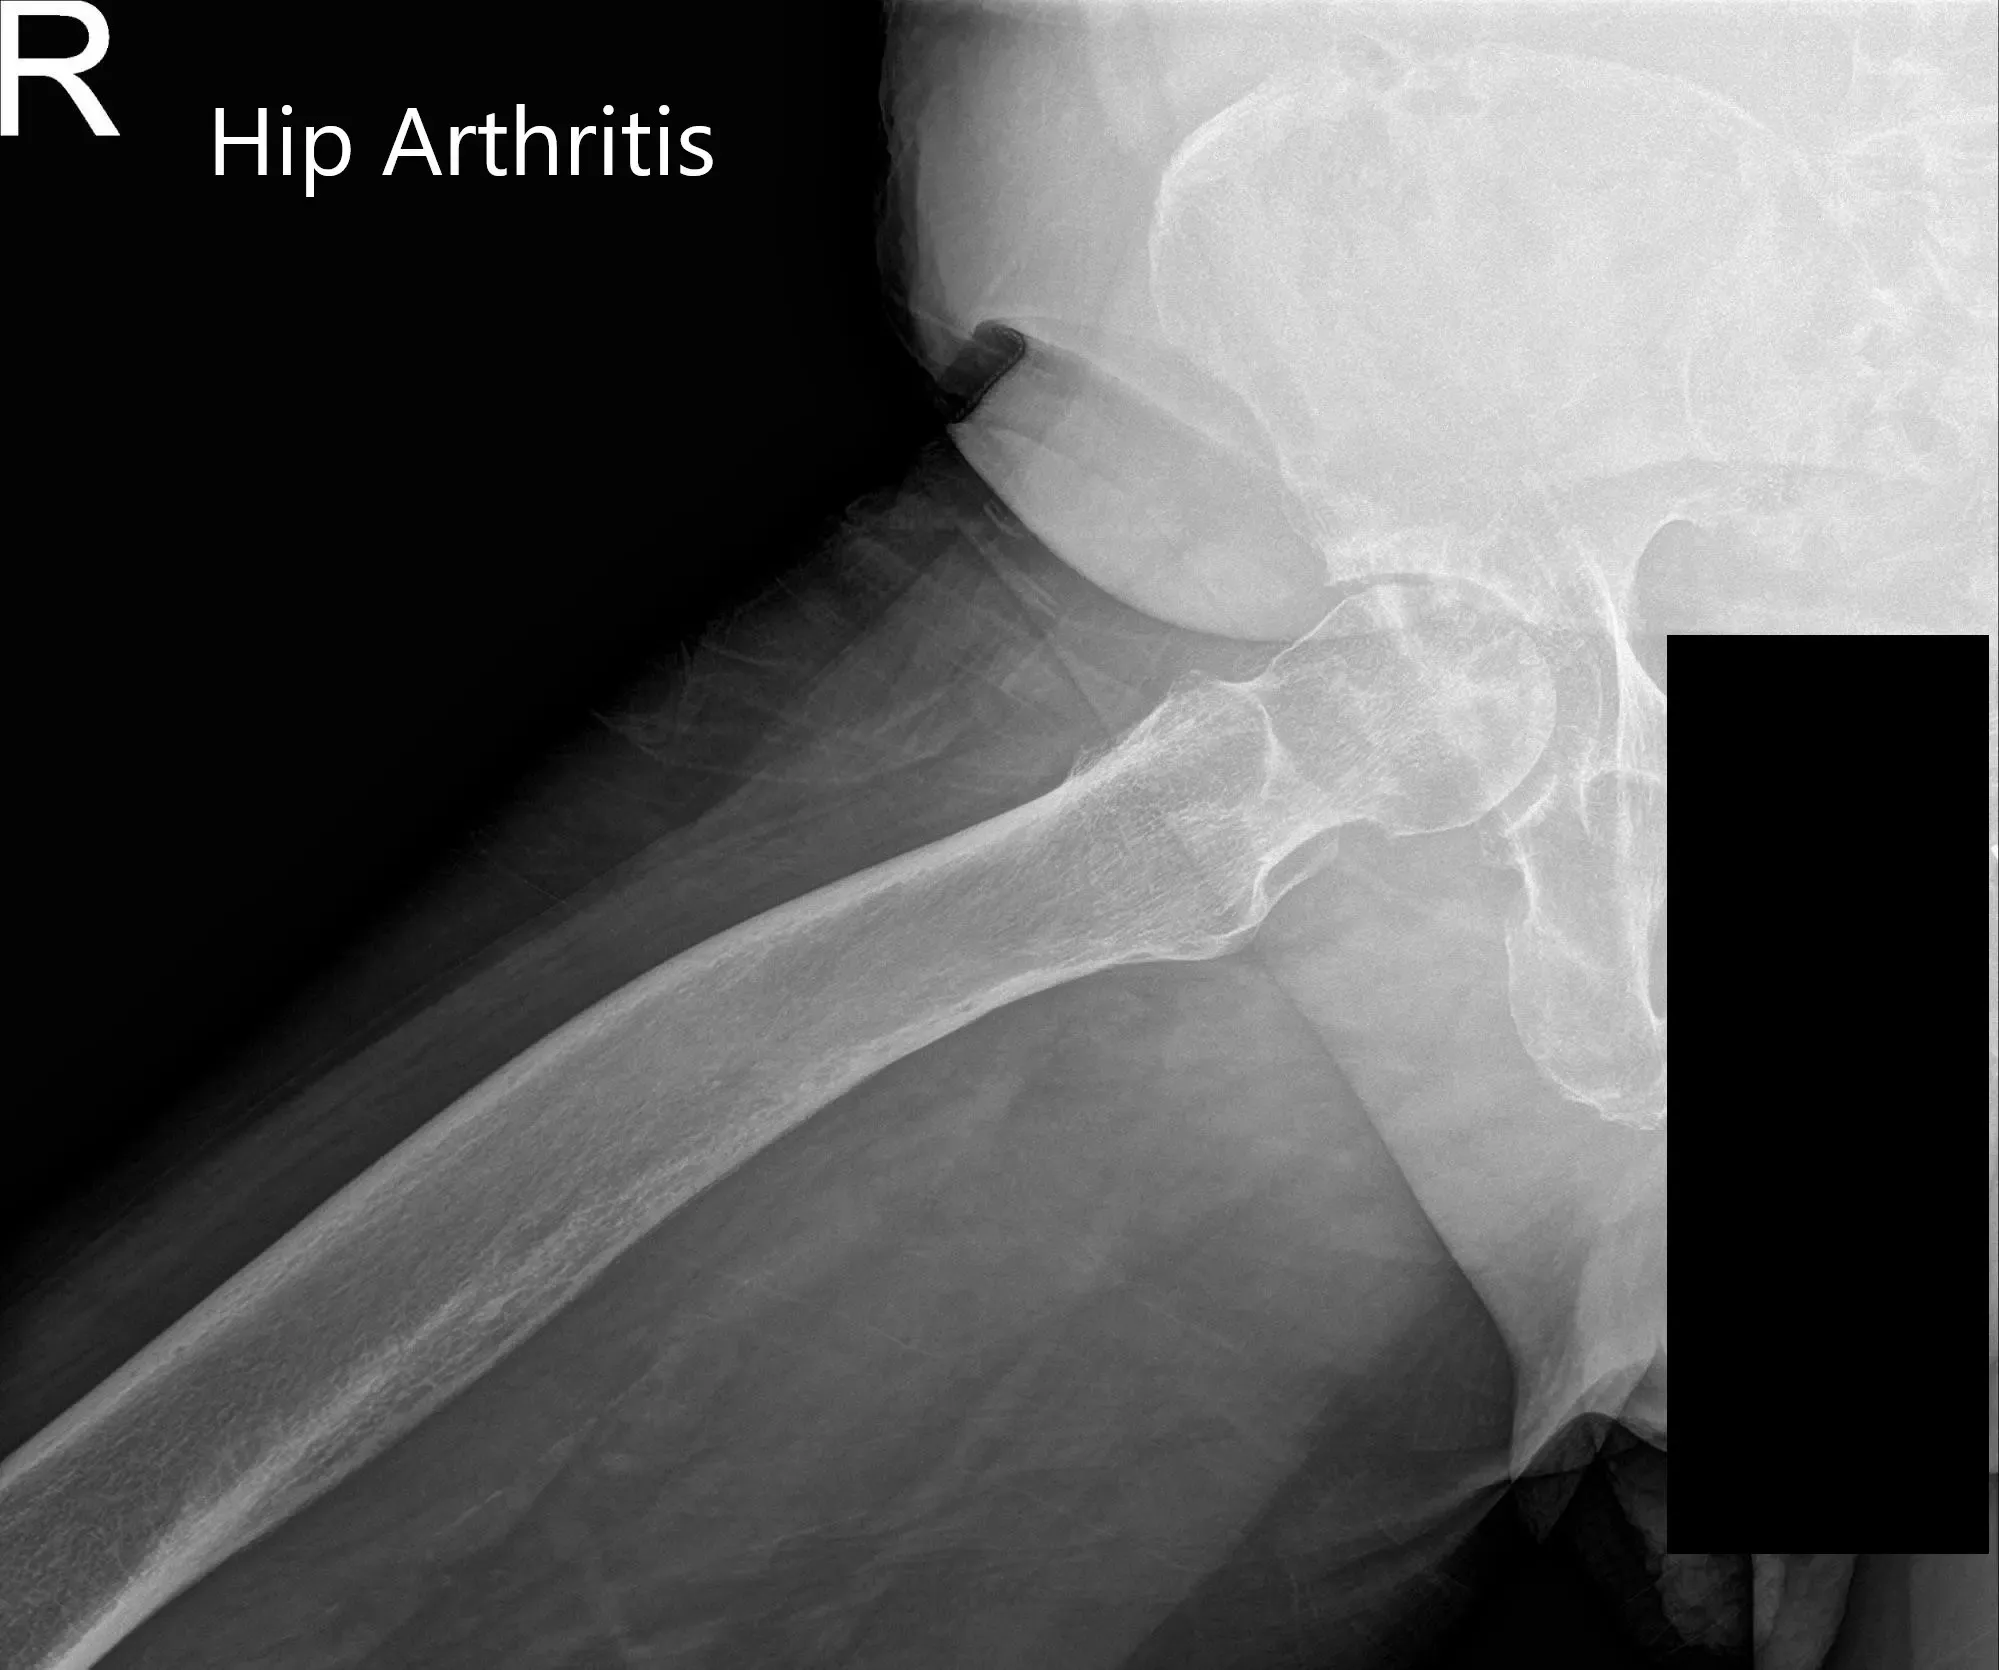

Preoperative X-ray of the pelvis, AP view, and frog-legged lateral view of the right hip.

Preoperative X-ray of Pelvis AP view and frog-legged lateral view of the right hip (image 2)